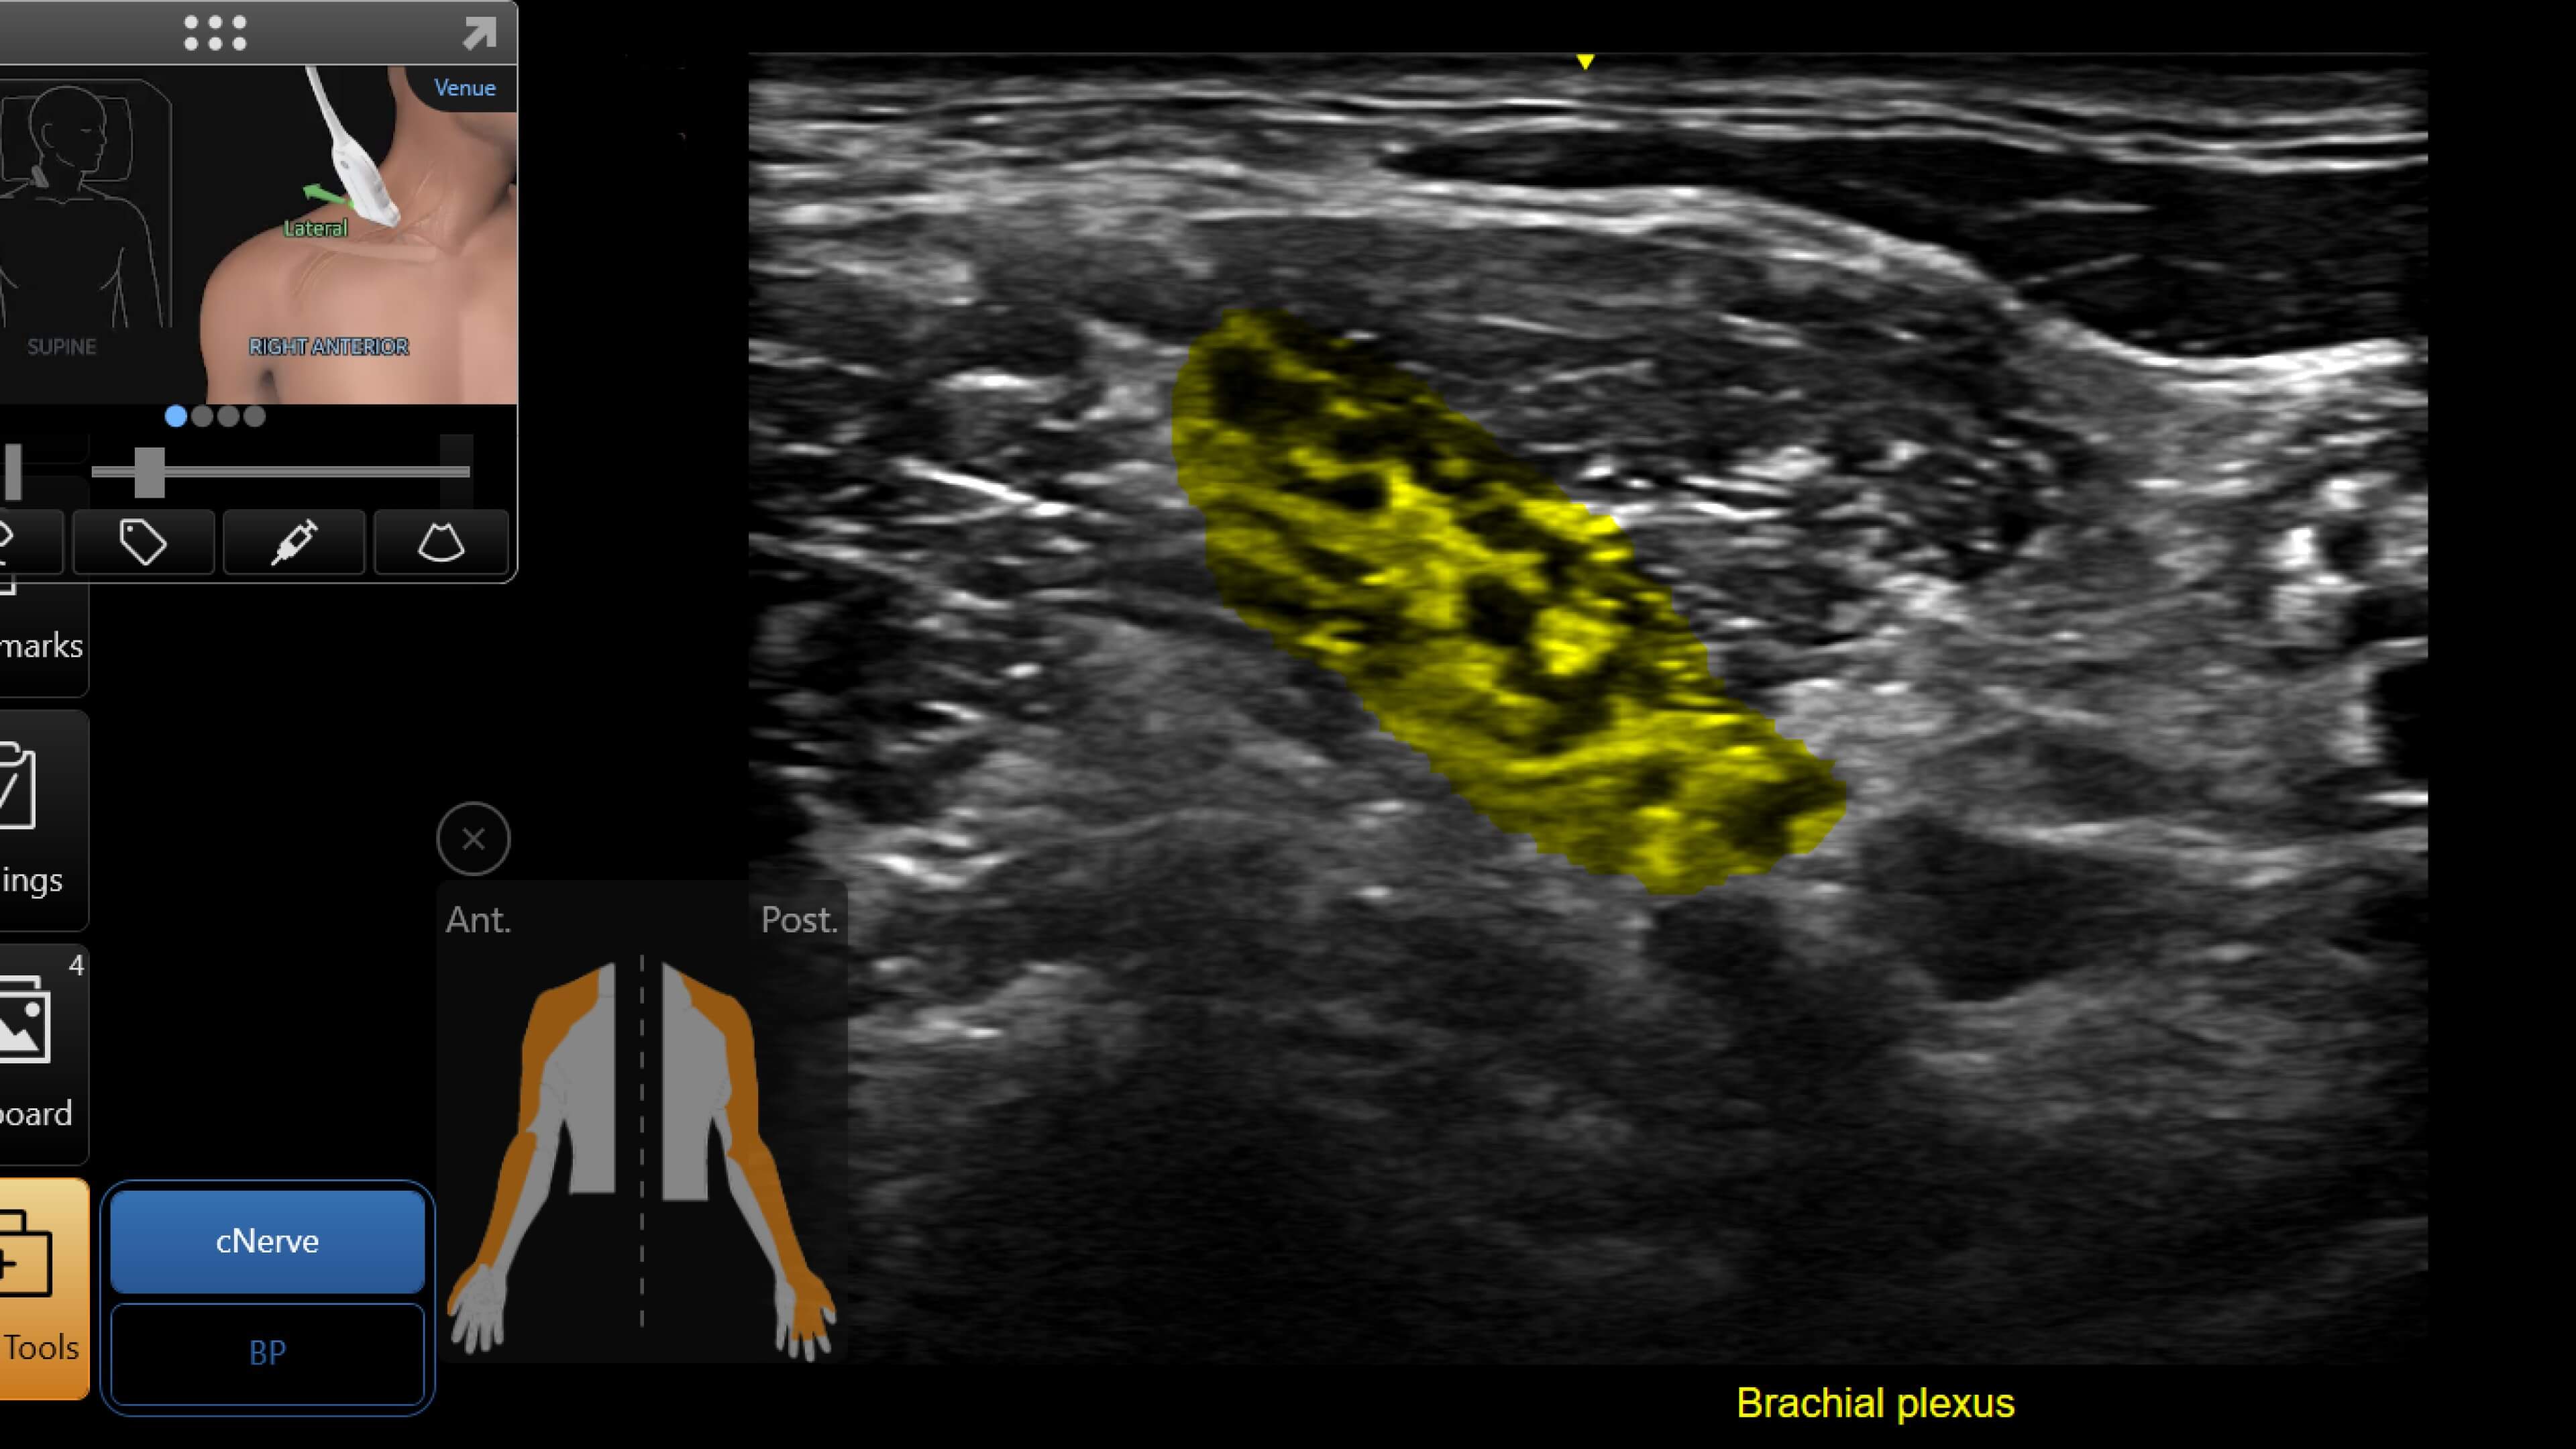

Vascular access

Helps you to assess vascular diseases, from cardiovascular conditions and peripheral vascular disease to pulmonary vascular disease.